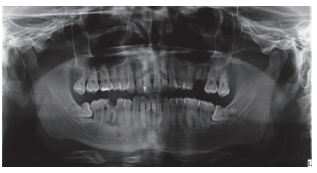

Caso clínico: se presenta el caso de un varón de 28 años, que acudió a consulta por la presencia de unos restos radiculares en localización de primer molar superior izquierdo. Se realizó un autotrasplante dental, siendo el diente donante el tercer molar superior izquierdo, que se trasplantó al alveolo del primer molar, mostrando buena evolución clínica y radiográfi ca.

Clinical case: a clinical case of a 28-yearold man is presented, who went to dental clinic for removal of left fi rst molar roots. An autotransplant was performed using left third molar as donor tooth, which was transplanted into fi rst molar alveolus, showing promising clinical and radiographic evolution.

Por tanto, debido a las altas tasas de éxito descritas en la literatura, el objetivo del presente caso clínico es evaluar clínica y radiográficamente la realización de un autotrasplante con el ápice cerrado, para reponer un primer molar superior izquierdo, como alternativa terapéutica a la colocación de un implante en un paciente adulto.